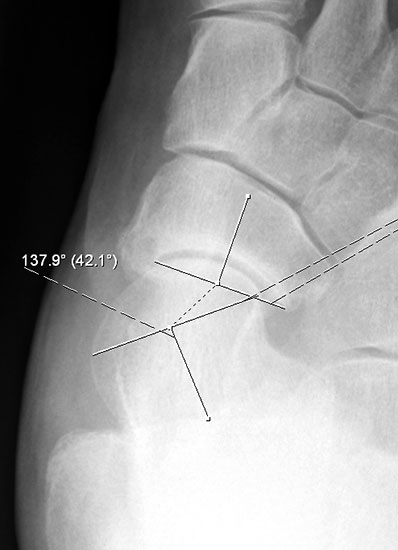

Der Talo-Metatarsale I Winkel bzw. die laterale talonaviculare Subluxation auf der stehenden dorsoplantaren Aufnahme des Fuβes dokumentieren das Ausmaβ des Vorfuβ abductus (Abb. 6 a,b). Ein dp Talo-Metatarsale I Winkel von > 10° (nach medial konvex) ist als pathologisch anzusehen. Mit der Bestimmung der talocalcanearen Divergenz (Abb. 6 c) erhält man ein Eindruck über das Ausmaβ des Rückfuβ valgus; eine leichte Divergenz bis ca. 12° gilt als physiologisch 20.

Auf der seitlichen, stehenden Aufnahme des Fußes wird ebenfalls der laterale Talo-Metatarsale I Winkel (Abb. 6 d) gemessen und so das kollabierte mediale Längsgewölbe dokumentiert. Auch hier gilt ein Talo-Metatarsale I Winkel von > 5° (nach plantar konvex) als pathologisch 21. Der Kollaps findet dabei meist im Talonaviculargelenk, seltener in der Naviculocuneiform-Gelenkreihe statt. Instabilität und Arthrose im 1. TMT sollten ausgeschlossen oder bei der Operationsplanung mit einbezogen werden. Weitere wichtige radiologische Messungen zur Beurteilung der Planovalgus-Statik und Progression der Deformität sind der laterale talo-calcaneare Winkel (Abb. 6 e) und der Abstand des Os cuneiforme-Unterrandes zum Untergrund (Abb. 6 f, Cuneiform height, 22. Eine anteriore Translation des Talus auf dem Kalkaneus findet man sowohl auf der ap, als auch auf der seitlichen Aufnahme des Fuβes mit Aufhebung der Cima-Linie.